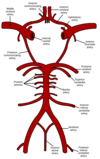

Hjärnans främre blodförsörjning kommer i grunden från a. carotis communis och än mer från a. carotis interna (avgår vid bifurkation vid 4:e cervikalkotan) på bägge sidor

- På höger sida avgår a. carotis communis från truncus brachiocephalicus

- På vänster sida avgår a. carotis communis från arcus aorta

Hjärnans bakre blodförsörjning kommer genom a. vertebralis som på bägge sidor utgår från a. subclavia

A. communicans posterior (2 st)

A. communicans anteror (1 st)

Hur löper a. vertebralis och vad bildar den?

Bägge sidor utgår från a. subclavia

- Går vanligtvis genom C1-C6 foramen transversarium på var sida och passerar bakom art. altantooccipitales genom foramen magnum

- Sedan förenas dessa vertebraler till en artär, a basilaris, vilket sker mellan medulla och pons

Hur löper a. basilaris och vad bildar den?

A. basilaris rider på pons och i övergången mellan pons och mesencephalon så delas denna upp i bifurkation till aa. cerebri posterior (PCAs)

Vad heter säkerhetssystemet där bakre- och främre blodcirkulation kommunicerar med varandra?

Cikulus Willisii